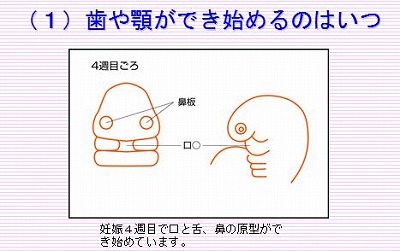

妊娠初期に胎児の歯や顎ができる またほ歯科ブログ